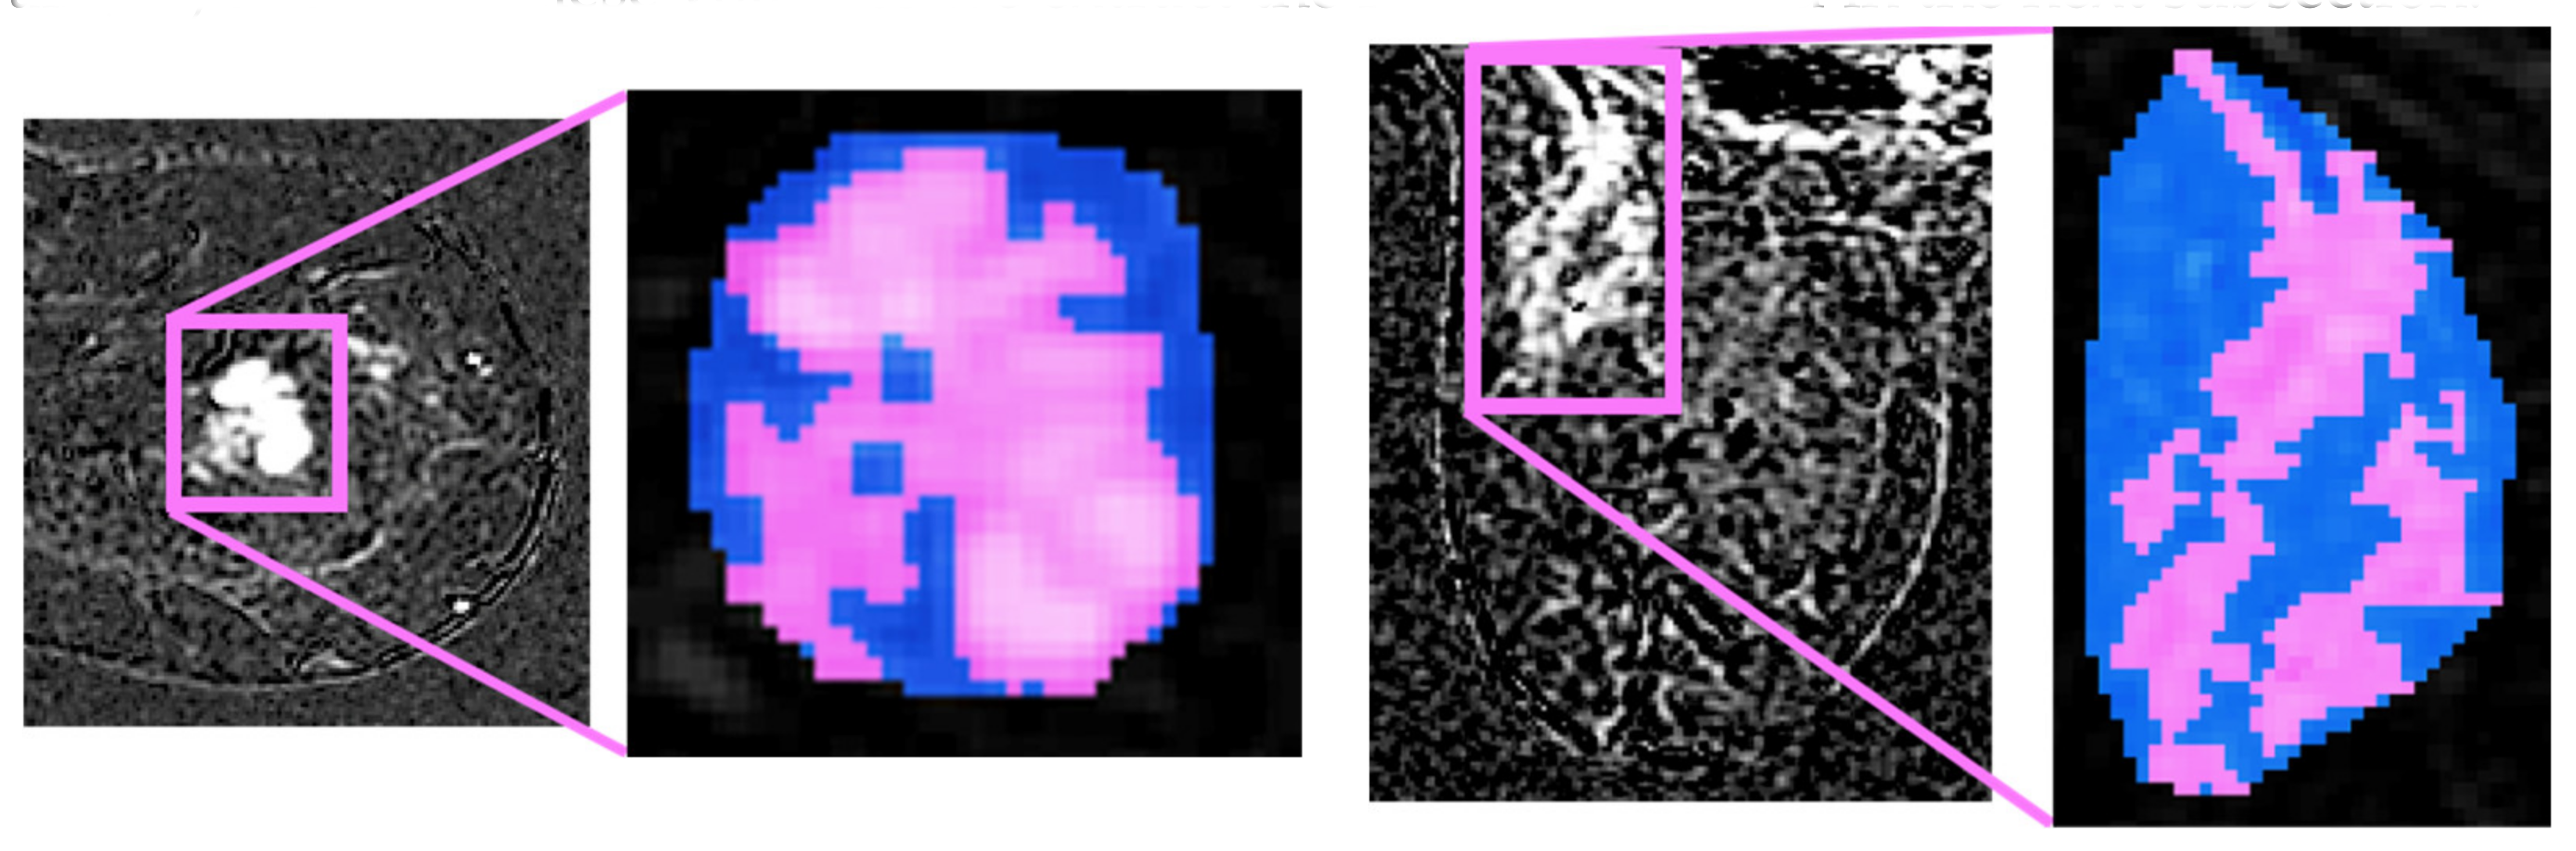

Figure 4. Four pre-processing examples. Left side halves: Bifocal lesion localized at upper-external quadrant, characterized by spiculated margins and IS/T curve. Right side halves: in pink, we highlight the original segmentation and, in blue, the convex hulls obtained.

Let us now focus on the segmented slices; we notice that the boundaries of each ROI are often coarse, affecting the quality of the features when calculated. This can be easily understood considering that many of the second-order measures presented in the following are computed from each voxel, considering also the other voxels in its neighbourhood. Before the feature extraction step, we pre-process the lesions’ contours to obtain a 3D volume with smoother edges, thus including large part of voxel neighbourhood. This is performed in two stages. First, we iteratively compute a 3D convex hull (CH), which is the minimum-volume bounded into a convex polygon and containing the ROI [22]; this process begins considering all not connected three-dimensional regions segmented using a default 26-connectivity. Second, all the 3D regions connected using a 26-connectivity are merged into a single volume, determining a new global CH. Such technique iterates until there are no more CHs left to merge, i.e., until the algorithm converges.

The CHs obtained so far are considered the definitive ROIs (Figure 4 depicts an example) and from these volumes we extract the features defined in the next subsection.

It worth noting the double benefit of applying of the described algorithm. Indeed, it is able to remove all the “outliers” from the ROI, i.e., all sub-volumes that are not large enough to delineate a CH. Moreover, the final volume integrates a slightly larger region surrounding the lesion, thus including all those voxels considered after the conversion of the ROI into a three-dimensional convex shape, and such extra tissue can bring useful quantitative information on how the tumour infiltrates during growth.